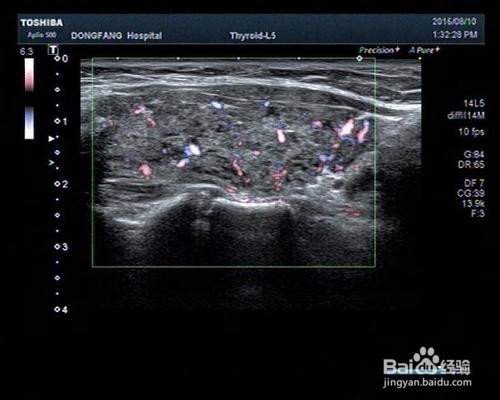

由于甲状腺疾病可导致甲状腺癌,虽然癌变几率非常小,但是也不能忽视,故可在半年复查一次甲状腺彩超,同时积极治疗机体的其他自身免疫性疾病。